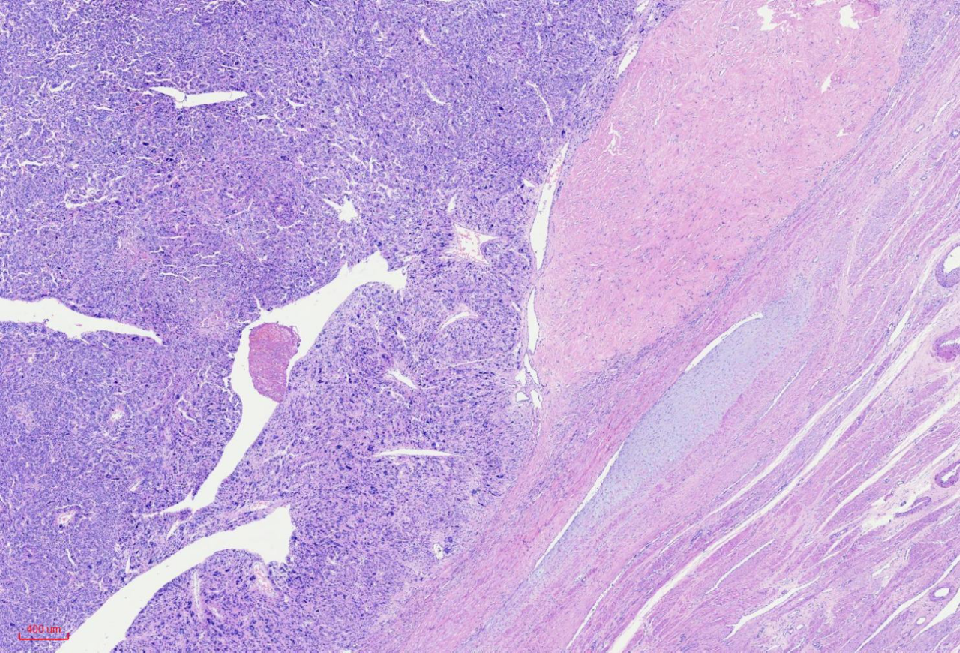

组织学改变

肿瘤与周围境界清楚

肿瘤细胞丰富

瘤细胞排列呈血管外皮瘤样

瘤细胞疏密相间

肿瘤境界清楚

细胞丰富

鹿角样/血管外皮瘤样血管

肺水肿样水肿/疏密相间

细胞核奇异,嗜酸性胞质,有显著的嗜酸性核仁,核仁周围可见空晕,部分细胞呈横纹肌样

核分裂象少见

无凝固性坏死